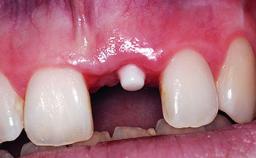

Replacement of a Failing Restored Upper Right Central Incisor, Ridge Preservation and Early Placement of an RC Bone Level Implant

A 23-year-old female, healthy and non-smoking patient had had tooth 11 temporarily restored following a trauma in adolescence. As the patient’s growth had since come to an end and the crown had fractured, she requested an implant-supported restoration of tooth 11. Moreover, the contralateral tooth 21 presented an old composite restoration at the mesial incisal edge. The periodontal tissues were healthy with periodontal probing depth values below 3 mm, but some inflammation was observed around the semi-submerged root of tooth 11.